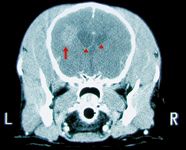

Recently, a technique has been developed that allows veterinary neurosurgeons to obtain a biopsy sample of the brain: a frameless stereotactic CT-guided needle biopsy.

Granulomatous meningoencephalomyelitis (GME) is a relatively common nonsuppurative inflammation of the brain, spinal cord, and meninges. The etiology is unknown.

Q: Could you provide a brief review on the causes and management of granulomatous meningoencephalomyelitis (GME) in dogs?